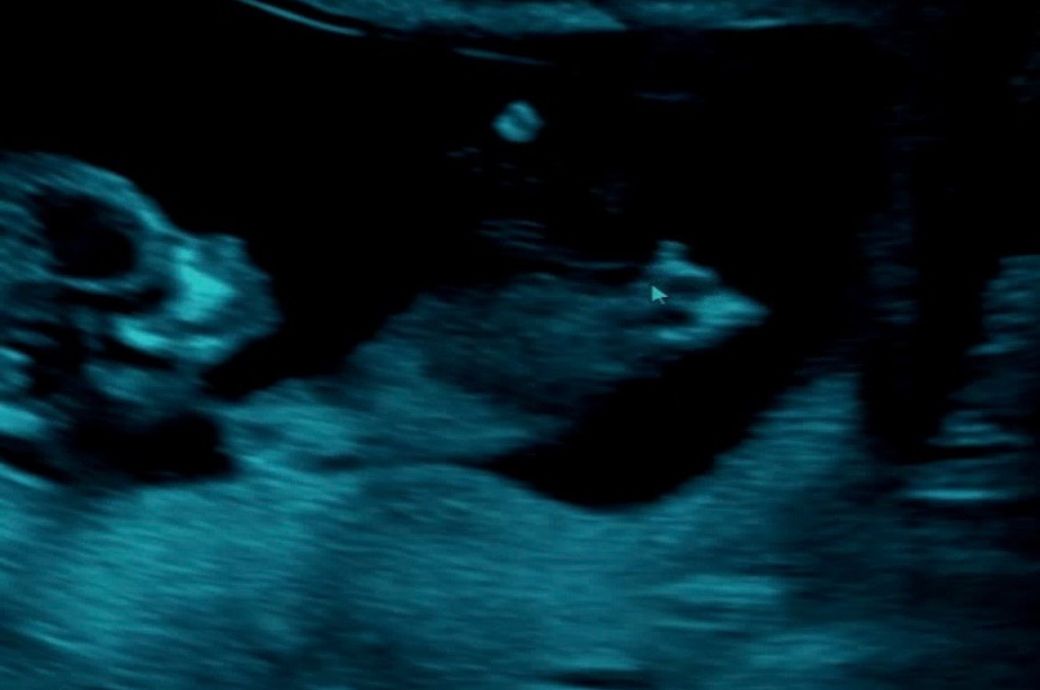

오늘(15주) 초음파 봤더니 딸이 거의 확실하다고 하시네요

초음파 사진 첨부합니다

왼쪽이 12주, 오른쪽이 15주에요

외부생식기가 늦게 발달하는 경우에 딸 -> 아들로 바뀌는 경우는 종종 있습니다만, 15주가 지나서 결정되는 경우는 드문 편입니다. 초음파 상에서도 외부생식기의 발달은 없는 것으로 보입니다.